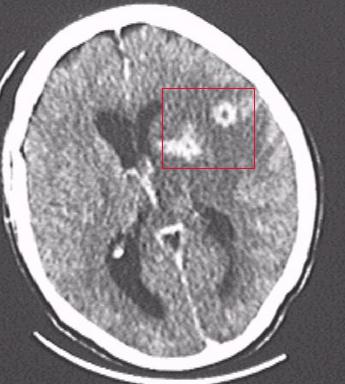

Формы токсоплазмоза. Осложнения

Сначала рассмотрим подробнее, к чему приводит запущенный токсоплазмоз. Симптомы у человека (фото на пленке посредством МРТ в разрезе) осложненного течения болезни в виде образований в мозговых оболочках просматриваются на нижеприведенном рисунке. Зона поражения обозначена красным квадратом, и она свидетельствует о развитии гнойного менингоэнцефалита. Этому состоянию могут сопутствовать осложнения — слепота, истощение, паралич. Смерть наступает от обширного и стремительно развивающегося поражения головного мозга.

Следует отметить, что токсоплазмоз мозга (симптомы и морфологические признаки) проявляется весьма разнообразно. Если проводить микроскопическое исследование, то наиболее характерными будут рассеянные по головному и спинному мозгу гранулемы, которые состоят из больших эпителиоидных клеток, лимфоцитов. Гранулемы заключают в себе паразитов и окружены отеками с очагами некроза.